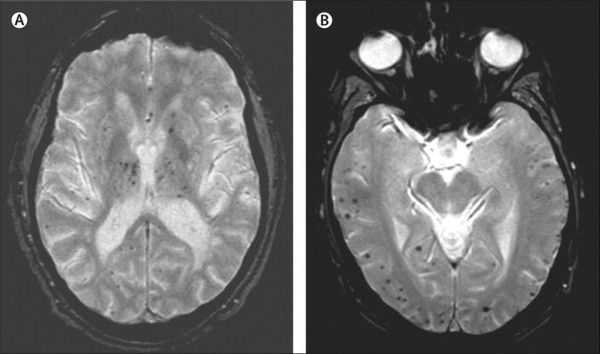

Описана смешанная модель патогенеза болезни Альцгеймера, которая предполагает взаимодействие церебральной амилоидной ангиопатии с сосудистыми факторами на ранних стадиях патологического процесса. Предполагается, что синергия между накоплением амилоида и цереброваскулярной патологией может инициировать дальнейшую дисфункцию нейронов и нейродегенерацию. [8] В этом отношении церебральные микрокровоизлияния, выявляемые в режиме Т2 градиентного эхо на магнитно-резонансной томографии, являются дополнительным и доступным диагностическим маркером, повышающим диагностическую значимость лейкоареоза и свидетельствующим в пользу церебральной амилоидной ангиопатии или гипертонической микроангиопатиии, особенно в случаях смешанной патологии и тяжелого когнитивного дефицита.

Локализация церебральных микрокровоизлияний является дифференциально-диагностическим признаком ведущего патологического процесса. В случае болезни Альцгеймера наблюдается корковая локализация микрокровоизлияний, в случае дисциркуляторной энцефалопатии или сосудистой деменции будут визуализироваться микрокровоизлияния в глубинных отделах мозга. [9] [10]